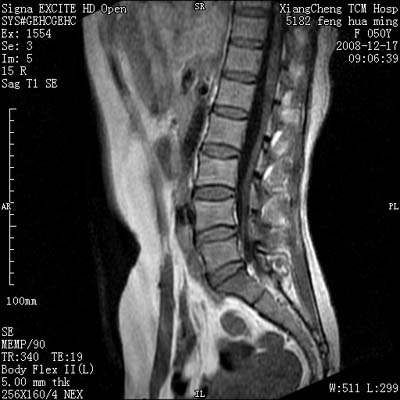

患者,女,50岁,左侧腹股沟及其下方疼痛、酸沉2年。

请各位战友看一下l4-5椎间盘后方椎管内是病灶吗?马尾神经到此处是不是终止了?

腰45椎间盘突出,后部影像可能是硬膜囊粘连引起的

l4/5椎间盘突出。后方硬膜囊受压改变。另外,该病人是否并发子宫肌瘤啊

腰45椎间盘突出,马尾终丝聚集:考虑蛛网膜炎症粘连

l4-5轻突,黄韧带增厚,蛛网膜炎症粘连可能

l4/5椎间盘突出;马尾终丝聚集,考虑蛛网膜炎所致。